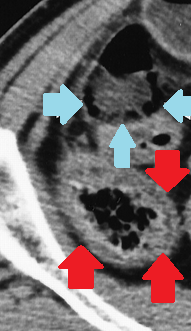

CT θώρακος 6η μετεγχειρητική ημέρα: αυξημένη συσσώρευση αέρα στο μεσοθωρακικό αιμάτωμα (κόκκινα βέλη) (Ευγενική παραχώρηση Dr. V. Penopoulos)

CT θώρακος 3η μετεγχειρητική ημέρα: Αορτικό stent σε θέση (κόκκινο βέλος). Ελάχιστος αέρας στο μεσοθωρακικό αιμάτωμα (πράσινο βέλος) (Ευγενική παραχώρηση Dr. V. Penopoulos)